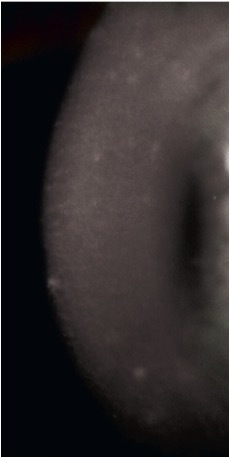

what does macular dystrophy look like?

diffuse, “ground-glass” haze lesions, corneal haze between lesions, gray/white or milky/white opacities throughout stroma and limbus to limbus